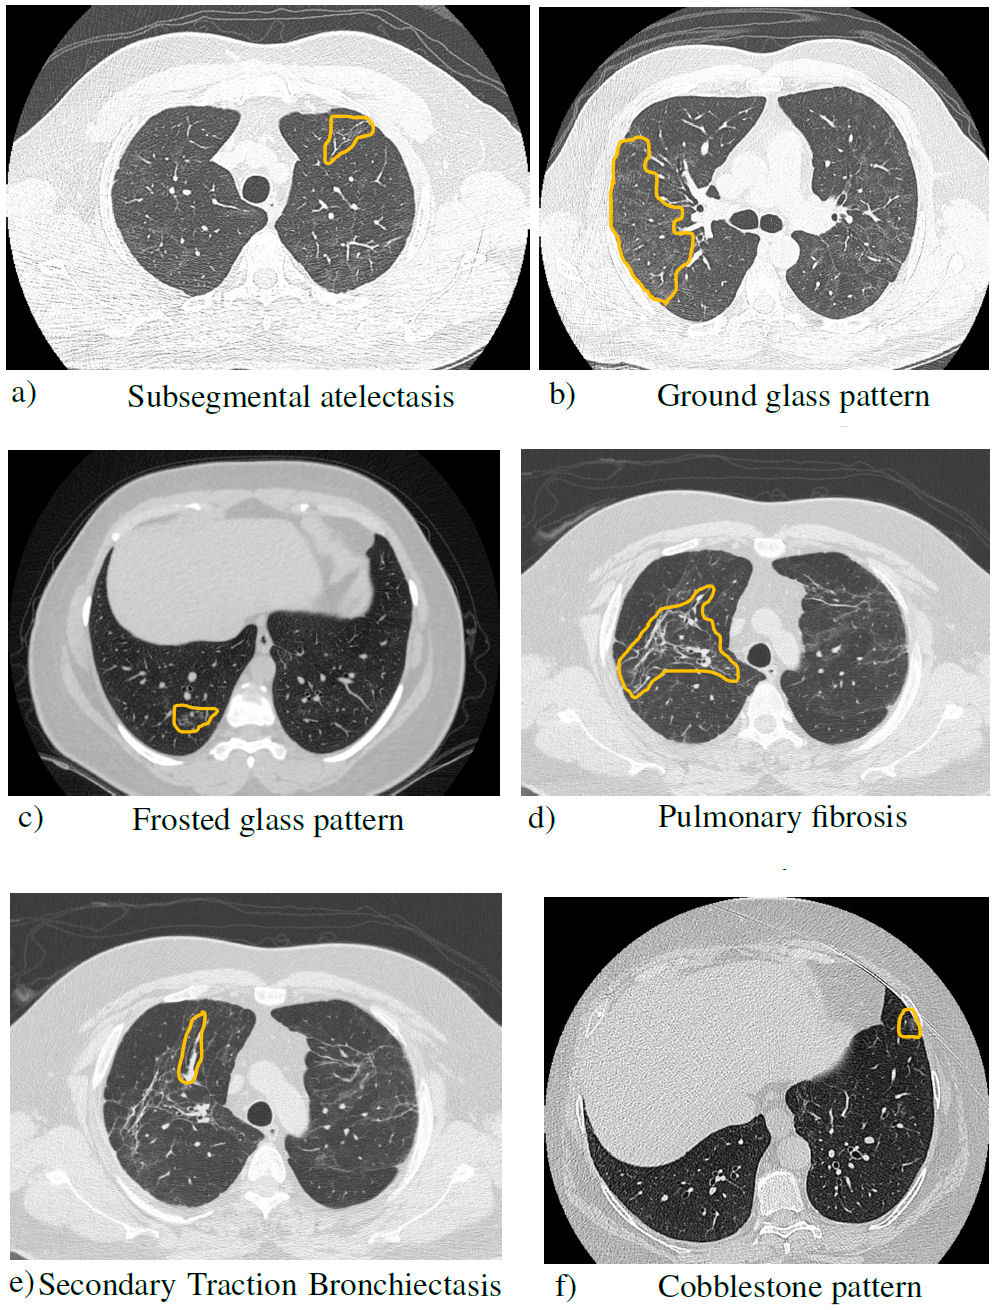

The different conditions observed by CT are listed in Table I [12].

TABLE I Brief description of the patterns found in the post-COVID computed tomography scans.

| Concept | Description |

| Subsegmental | Partial collapse of a |

| atelectasis | part (segment) of the lung. |

| Ground/Frosted | Area of greatest pulmonary attenuation |

| glass pattern | within which the vascular structures can be visualized since they are not erased. |

| Pulmonary | It occurs when lung tissue is damaged, and |

| fibrosis | scarring occurs. This thickened, stiff tissue makes it harder to breathe and the blood doesn’t get enough oxygen. |

| Secondary | Airways are dilated by |

| Traction | parenchymal distortion because |

| Bronchiectasis | of pulmonary fibrosis. |

| Cobblestone | The reticular pattern often with the |

| pattern | appearance of interlobular septal thickening, superimposed on ground-glass opacities, simulating cobblestones. |

Figure 5 shows the most common findings from the dataset of Mexican patients.

FIGURE 5 Simple chest tomography with lung window in axial section, where the findings of the pathologies are observed.